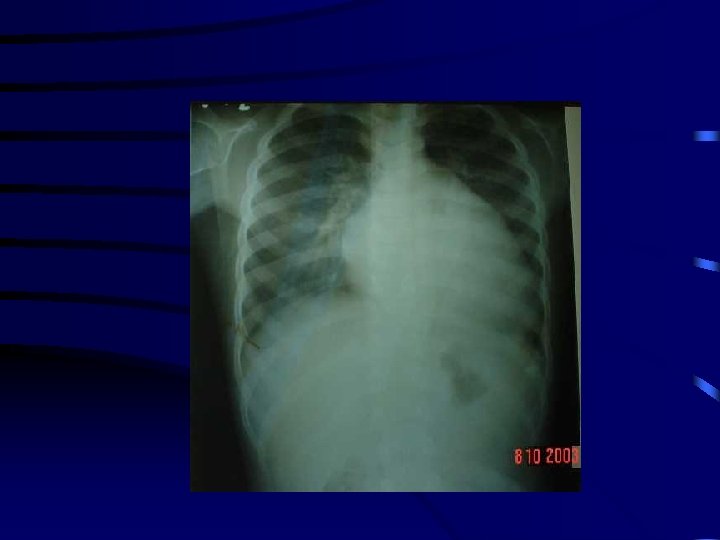

Radiografía de tórax • Crecimiento aurícula izquierda • Doble contorno de borde cardiaco derecho • Rectificación de borde cardíaco izquierdo • Prominencia de arterias pulmonares • Desplazamiento hacia arriba de bronquio izq, hacia la izquierda de la aorta, hacia atrás el esófago • Ensanchamiento de cavidades derechas • Ventrículo izquierdo normal

RX TORAX • Congestion pulmonar • Edema intersticial • Edema alveolar Presion AI >18 mmhg >25 mmhg >35 mmhg

EDEMA PULMONAR